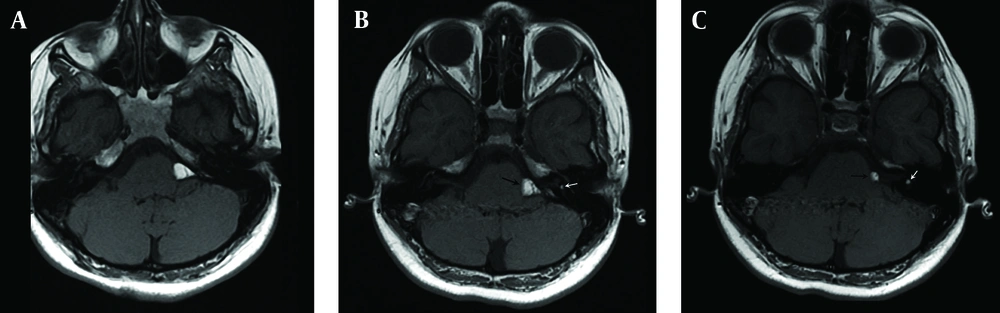

The patient was subjected to radiological examination and computed tomography revealed a homogeneously hypoattenuated CPA mass (Figure 1). MRI showed a hyperintense 15×7 mm sized left CPA mass that encased the left VIII cranial nerve on T1-weighted images. The mass signals were suppressed on fat saturated images. The eighth cranial nerve was followed up and a 4 mm diameter lesion with a similar radiologic feature in IAC was seen (Figures 2 and 3). After administration of contrast with fat suppression, axial T1-weighted image displayed suppression of the CPA and intravestibular mass, and no enhancement was observed (Figure 4). These findings together with the confirmation on fat suppressed images were highly suggestive of a lipoma. Our patient was followed up clinically and radiologically for two years and there has been no progression.

A) Axial T1-weighted image shows a hyperintense mass due to lipoma in the left cerebellopontine angle (curved white arrow) and left internal acoustic canal (straight white arrow). B) Axial T1-weighted image with fat saturation displays saturation of lipomas in the left cerebellopontine angle (curved white arrow) and left vestibule (straight white arrow). C) Enhanced axial fat saturation T1-weighted MR image shows no enhancement of lesions